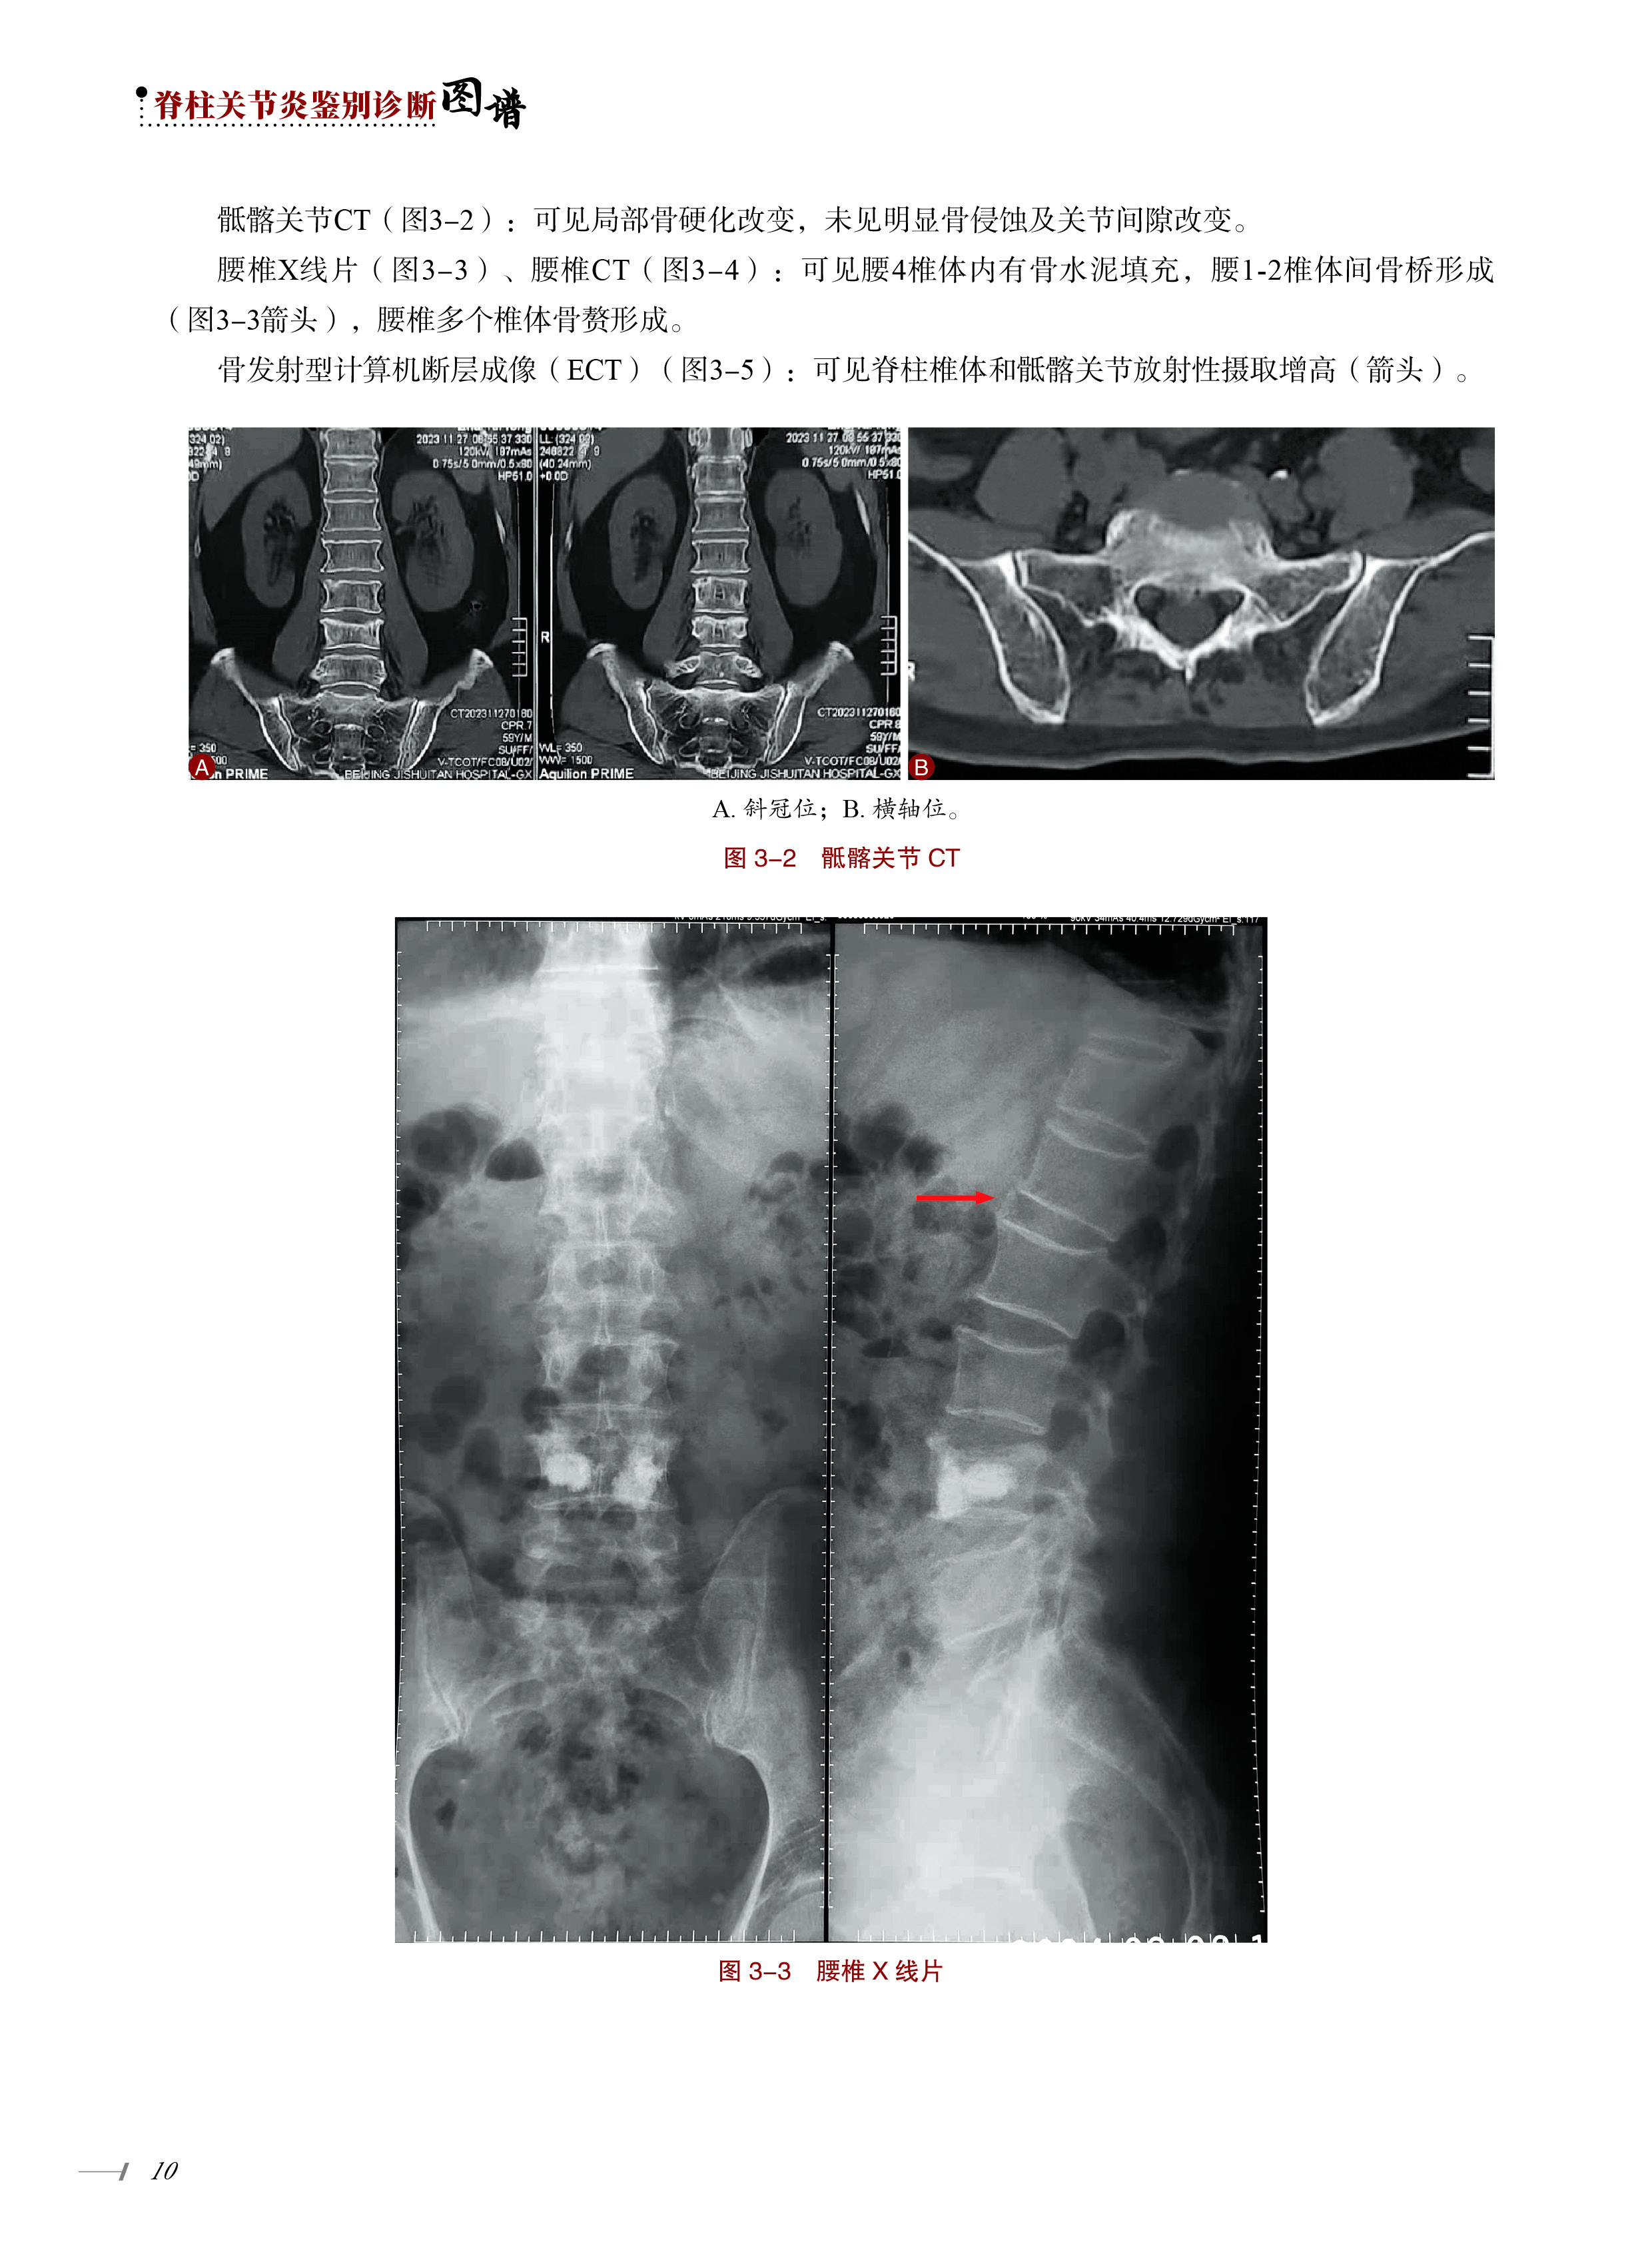

案例3 老年男性-慢性腰痛-虹膜炎 9